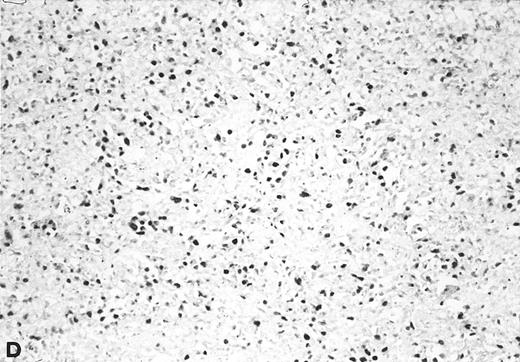

In situ hybridization with EBER probes. In a representative lymphadenopathy case (no. 20), rare EBER+ cells are seen, mainly in the interfollicular areas (A and B). In a representative lymphoma case (no. 46) nearly half of the cells are EBER+ (C and D). Original magnification: ×130 (A and C) and ×260 (B and D).

Twelve of the 16 EBV+ lymphoma samples scored from 3+ to 6+ for EBV DNA content (ie, 102- to 105-fold higher than that found in the majority of the lymphadenopathy samples), and most were also positive by Southern blot analysis (Table 4). Seven of 11 tested samples were also positive for viral sequences by in situ hybridization with EBER probes (Table 4). Although the high content of EBV in these tumors strongly indicated that they arose from the proliferation of EBV+ cells, 4 large cell lymphomas contained consistently low levels of EBV DNA, a finding that might reflect either a dilution effect by nonneoplastic EBV− cells in the analyzed samples, or the presence of few infiltrating reactive EBV+ B cells.